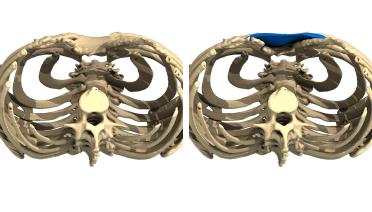

La tecnica di impianto su misura è una tecnica chirurgica minore che consiste nel riempire la concavità creata dal Pectus con un impianto personalizzato. Si tratta di un intervento rapido, a basso rischio, con un risultato immediato e una breve convalescenza.

In questa pagina, troverà i risultati di questa operazione a seconda del tipo di Pectus : mediale, asimmetrico, più o meno profondo o lungo.

Tipo 1 : Mediano, profondo e simmetrico,